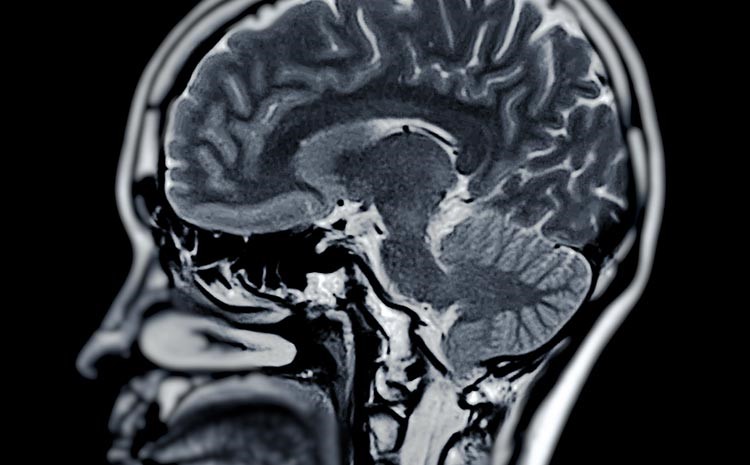

O cérebro é um dos órgãos mais complexos do corpo humano. Sua estrutura é formada por bilhões de células nervosas interligadas, responsáveis por pensamentos, movimentos, emoções e memórias. Qualquer intervenção...

O cérebro humano é alimentado por uma rede complexa de vasos sanguíneos que levam oxigênio e nutrientes essenciais para seu funcionamento. Embora essa rede seja incrivelmente bem projetada, eventualmente...